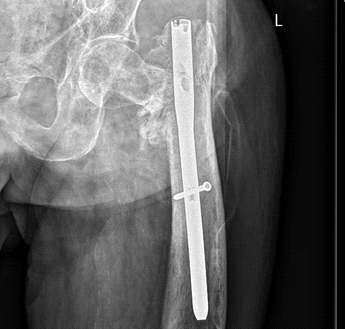

螺钉取出后的X线片显示骨折不愈合。